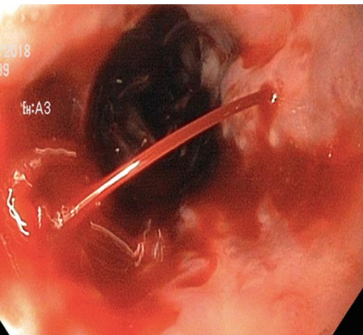

Endoscopic image after performance of splenectomy. Complete disappearance of the varices of the fundus of the stomach (Courtesy Dr. V. Penopoulos)